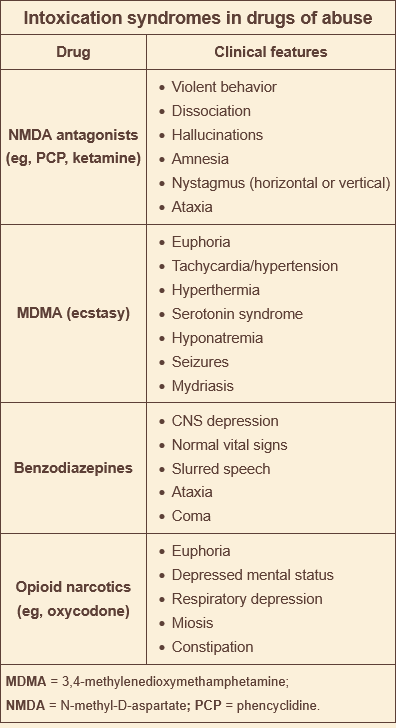

_____ is a recreational party drug that can cause serotonin syndrom

ecstasy